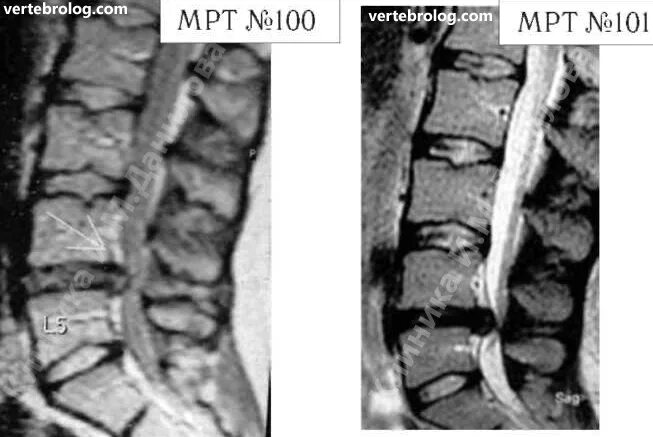

Грыжа диска мрт